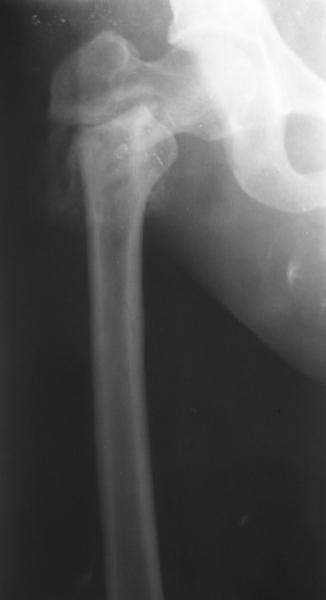

Уважаемые коллеги, хотелось бы услышать ваше мнение по следующему случаю: Относительно молодая женщина(39 лет), поступила в клинику в марте 2005 года, через 3 месяца после травмы с Неправильно срастающимся поперечным межвертельным переломом правого бедра. Был выполнен закрытый интрамедуллярный остеосинтез правого бедра канальным реконструкционным стержнем ChM. Ожидали бОльших проблем на операции, результату обрадовались. Как оказалось, зря. Сращение наступило через 3,5 месяца после операции. В ноябре 2005 года произошел перелом шейки бедра и винтов в ней. В апреле 2006 импланты были удалены. В приложении фото и рентгенограммы больной. Сопутствует ожирение 4 ст. (при росте 168 см., вес больной 140кг.), сахарный диабет II тип. Имеется медиальная неустойчивость коленного и голеностопного суставов, при нагрузке колено вальгируется на 15-20 градусов. Вопросы: 1.Целесообразность эндопротезирования (в настоящий момент передвигается на ходунках)? 2.Если ответ на первый вопрос-да, то каким протезом? 3. С какими проблемами можем столкнуться во время и после операции? Заранее благодарен за ответы. Салават Салаватов, Екатеринбург

Если осознанный выбор пациентки на лечение, то протезирование т\б сустава не таит в себе огромных сложностей - только глубина операционной раны и рубцово измененные ткани. Учитывая проксимальный дефект бедренной кости предпочтительна ревизионная ножка ZMR ZIMMER. Чашка любая безцементная.